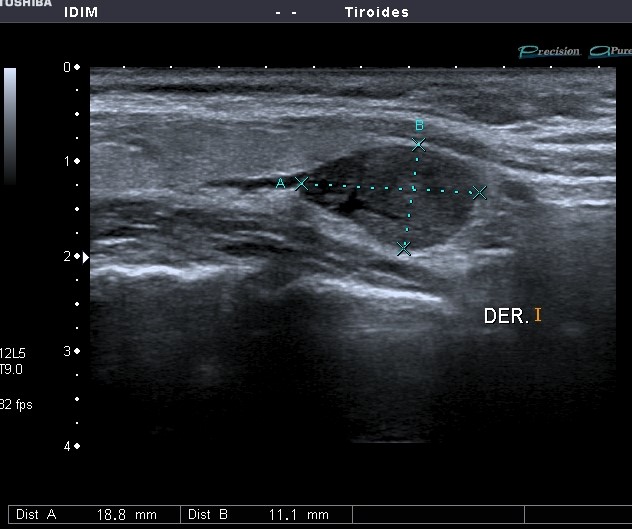

Se realizó ecografía tiroidea y partes blandas de cuello: nódulo hipoecoico de forma ovalada, aspecto sólido, con presencia de vascularización en su interior, con patrón NO hiliar. Medía 18.8mm (A) x 11.1mm (B). Se ubicaba posterior e inferior al lóbulo tiroideo derecho y presentaba límites definidos con plano de clivaje con tiroides.

Diagnóstico anatomo patológico post operatorio: Adenoma paratiroideo